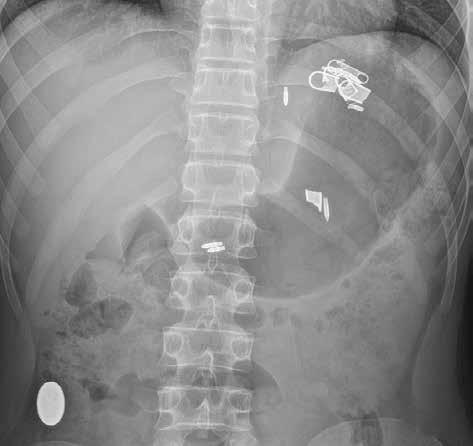

2.1 Prostý RTG snímek

Prostý snímek břicha je stále jednou z nejlevnějších a nejdostupnějších zobrazovacích metod, využívaných při vyšetření nemocných s náhlou příhodou břišní. I když jeho význam klesá a dnes toto vyšetření nelze považovat za „metodu první volby“, má přesto i v době výpočetní tomografie (CT), ultrazvuku (UZ) a MR (magnetické rezonance) využití při podezření na střevní obstrukci či perforaci trávicí trubice, při hodnocení polohy drénů nebo detekci rentgenkontrastního tělesa (obr. 1).

Můžeme provést předozadní snímek vleže na zádech a/nebo zadopřední snímek vestoje v závislosti na indikaci vyšetření. U nemocných ve vážném stavu lze snímkování provádět přímo na lůžku, ovšem za cenu jeho nižší kvality. Prostý snímek břicha vleže na zádech má větší výpovědní hodnotu a standardně i vyšší kvalitu. Přesněji na něm můžeme posoudit šířku lumen tenkého i tlustého střeva. Vzduch tvoří negativní kontrast, který umožní částečně hodnotit šíři střevní stěny i řas. Lépe než u snímku vestoje lze také zhodnotit rozložení plynné náplně střev, a tím i snáze lokalizovat přechodové zóny (obr. 2).

Snímek břicha horizontálním paprskem vestoje se provádí s cílem zobrazit hladinky a volný vzduch v dutině břišní. Jako hladinky označujeme tzv. hydroérický fenomén neboli rozhraní mezi tekutinou a plynem v lumen střeva (obr. 3). Fyziologicky obsahuje tenké střevo cca 200 ml vzduchu a 2000 ml tekutiny, která však stále cirkuluje. Hladinky, které se na hranici tekutina/plyn ve střevních kličkách tvoří, můžeme zachytit i u zdravého jedince, u pacientů s malasimilačním syndromem a u nemocných s paralytickým ileem. Nejčastěji se s hladinkami setkáváme u nemocných s mechanickou překážkou střevní průchodnosti. Někdy lze podle lokalizace a tvaru hladinek odhadnout místo a příčinu poruchy střevní pasáže. Při akumulaci tekutiny a vzduchu v lumen střeva dochází k jeho dilataci na 3,5–4 cm (někdy až 5 cm i více). K distenzi trávicí trubice dochází orálně od místa obstrukce.

Volný vzduch v peritoneální dutině je většinou známkou patologické komunikace trávicí trubice s volnou dutinou břišní (obr. 4). Pravidelně ho vídáme po břišních operacích, zejména po laparoskopii. U prostého snímku břicha horizontálním paprskem je centrální paprsek zaměřen do středu spojnice hřebenů lopat kyčelních, a subdiafragmatický prostor je tak zobrazen zespodu šikmo, a ne tangenciálně. Výsledkem je superpozice s masou celých jater a sumace především s dorzálním diafragmatickým recesem, vyplněným vzdušnou plicní tkání. Větší diagnostický význam při detekci plynu pod bránicí má proto prostý snímek hrudníku vestoje. Volný plyn je detekovatelný i na snímku břicha vleže na zádech (znamení dvojité stěny – „double wall“ sign) (obr. 5). Malé množství volného plynu v dutině břišní je však takto nezobrazitelné. Také srůsty mohou bránit migraci plynu do podbráničních prostor, a tím zvyšovat falešnou negativitu vyšetření. Nejčastějšími příčinami pneumoperitonea jsou perforace trávicí trubice (vředová choroba gastroduodenální, komplikovaná divertikulitida, traumatické či iatrogenní příčiny). Kromě trávicí trubice

Obr. 1: RTG snímek břicha vleže. Stíny několika cizích těles – pružinka, hroty propisovací tužky a úlomky zipu v žaludku. Oválný stín (knoflíku podle anamnézy) v colon ascendens.

Obr. 2, 3: RTG snímek břicha vleže a vestoje. Ileus tenkého střeva. Vleže je dobře patrná dilatace kliček tenkého střeva nad 3 cm (2). Tenké střevo odlišíme od tlustého přítomností plicae circulares, které obkružují celý obvod lumen střeva. Vstoje vidíme v tenkém střevě hladinky (3).

Obr. 4: RTG snímek břicha vestoje. Pneumoperitoneum. Srpovité projasnění volného plynu pod pravou brániční kopulí.

Obr. 5: RTG snímek břicha vleže. Pneumoperitoneum. Žluté šipky označují místa, na kterých je střevní stěna ohraničena jednak plynem v lumen střeva, jednak volným plynem v okolí. 1